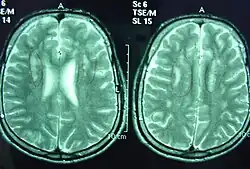

T2-weighted MRI images of a 25-year-old male with Sjögren–Larsson syndrome revealing dysmyelination in the deep periventricular white matter and reduced brain volume in the frontal lobe